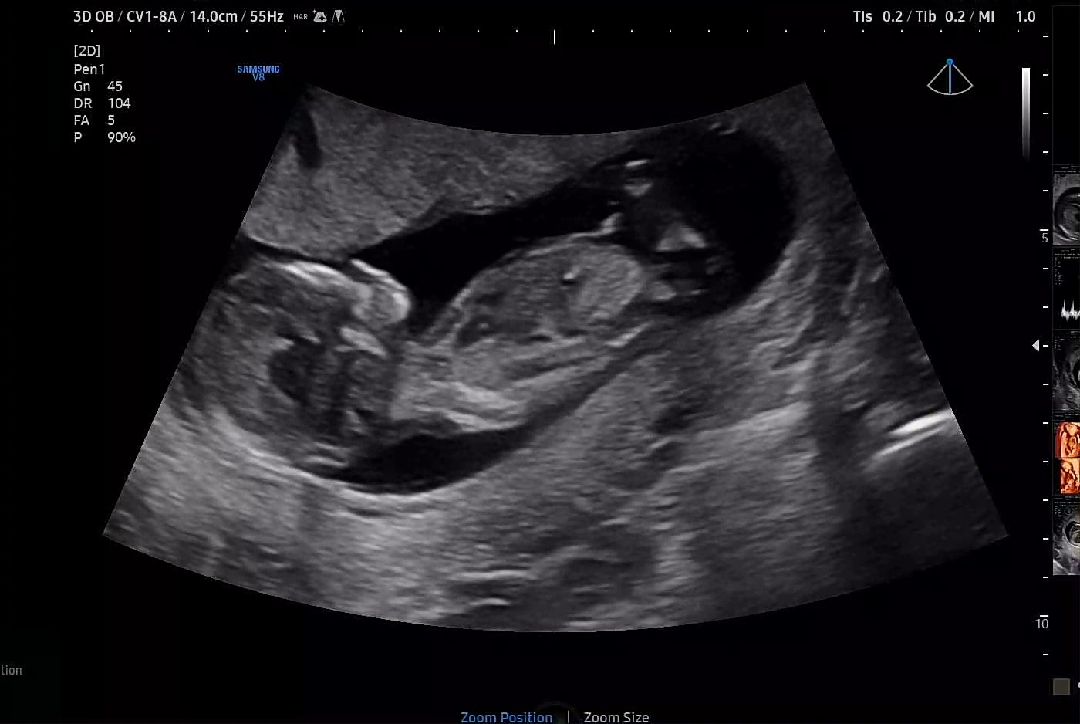

12주4일 성별 투표 부탁드립니당♡

혹시 예측가능한 맘님들 있을까요~? 투표좀 부탁드립니당♡♡